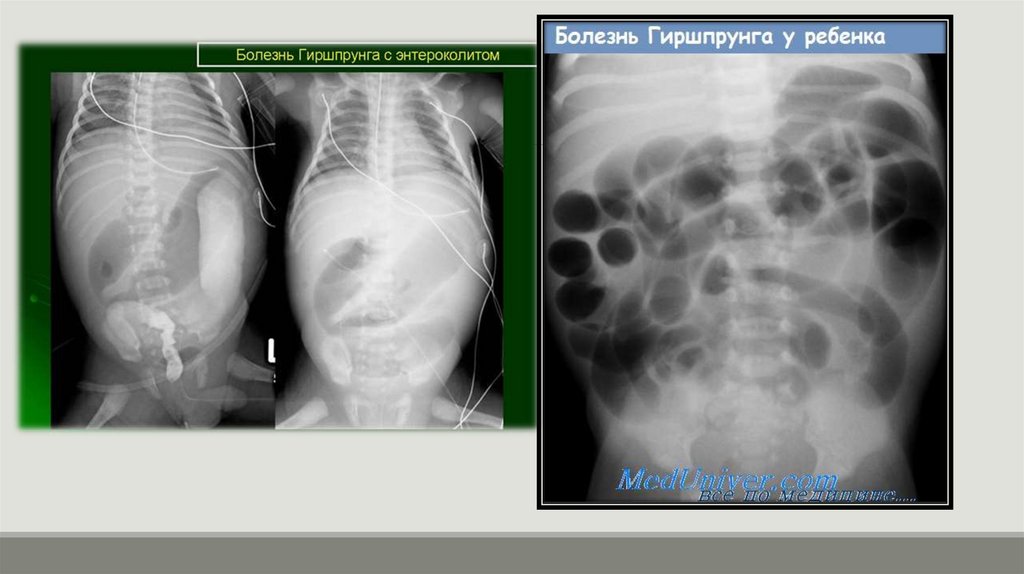

10. Болезнь Гиршпрунга (Аганглиоз)

Врожденный порок развития дистальных отделов кишечника,

характеризующийся отсутствием нервных ганглиев в подслизистом и

мышечном сплетениях стенки кишки.

Суть патологии:

Пораженный (аганглионарный) отрезок кишки постоянно находится в

состоянии спазма и не перистальтирует, так как не получает сигнал к

расслаблению. Это создает функциональное препятствие для

пассажа кишечного содержимого. Вышележащие, отделы кишки

расширяются (формируется мегаколон – "гигантская кишка").

Локализация: В 80% случаев поражается ректосигмоидный отдел.

Клиническая картина:

· У новорожденных: Задержка отхождения мекония (более 24-48

часов), рвота с желчью, вздутие живота.

· У детей старшего возраста: Хронические запоры с рождения,

прогрессирующее вздутие живота, симптомы интоксикации,

отставание в развитии.